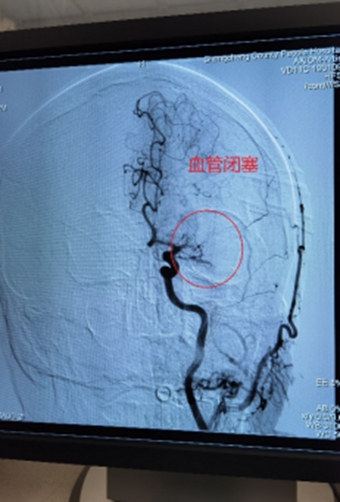

1、左侧颈内动脉末端闭塞,急诊导管抽栓+支架拉栓1例;